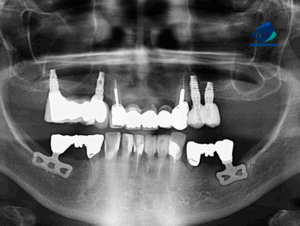

Paciente femenino de 58 años acude al Instituto de Diagnostico Maxilofacial para realizarse una tomografía para la colocación de implante dentales. A la evaluación de